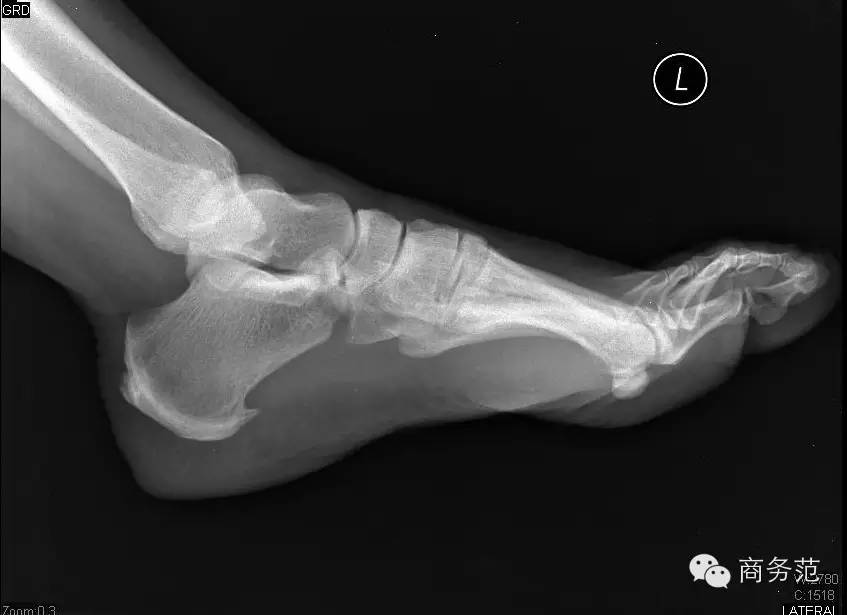

不少骨科和腱炎专家表示缺乏足弓的鞋子穿久了会很累,而UGG是平底鞋,而且鞋内空间相对大,每走一步重力都会散开,足弓无支撑会承受较大的大冲击。

若长时间穿无足弓的鞋子对足部,脚踝,臀部,脊椎都会造成伤害呢 _(:зゝ∠)_